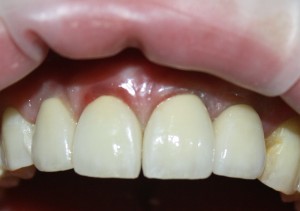

К счастью, уже через 6 недель после операции вдруг выяснилось, что ничего исправлять не нужно:

Фактически, нам осталось лишь дождаться приемлемого уровня остеоинтеграции имплантатов,  — примерно 2-3 месяца, — и можно переходить к постоянному протезированию.

Через три месяца мы сняли коронки с имплантатов, чтобы оценить качество формирования десневого контура:

С этого момента можно перестать переживать — десневой контур сформировался правильно, мы получили достаточный объём и качество окружающей платформу имплантата десны. Можно приступать к изготовлению постоянной протетики. Подрядчиком стала зуботехническая лаборатория French Creative, одна из топовых лабораторий Москвы.